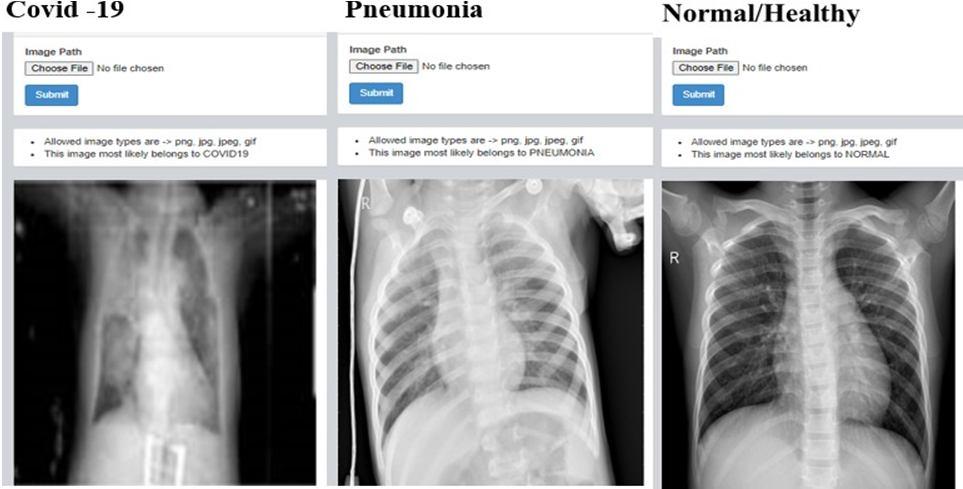

G. Results of web application

1) Detection of Covid 19 , Pnuemonia and Healthy chest x ray: Here the X ray images are fed by clicking on choose file in dash board after that we need to select file in which the images are present and upload it once after uploading needto click on submit button once after the submiting image we can observe result whether the given X ray belong to covidor pneumonia or normal.The same procedure is followed for many iteration to check whether develop web application is accurate by feeding different types of X ray images.

Fig. 18: Iteration 2 Fig. 19: Iteration 3 Fig. 20: Iteration 4

Fig. 21: Iteration 5